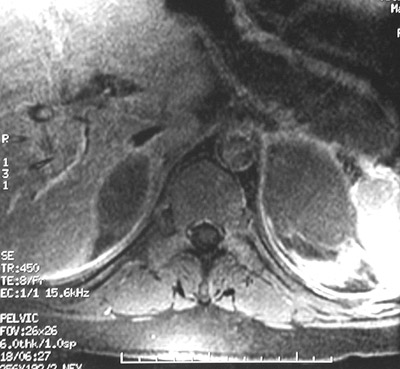

| The abdominal spin echo T1 weighted MRI scan above reveals bilateral adrenal hemorrhages on the right and on the left. In addition to meningococcemia, other etiologies could include coagulopathy, hemorrhagic cortical carcinoma, and adrenal vein thrombosis with infarction. The view below is a fast spin echo T2 weighted MRI scan. |